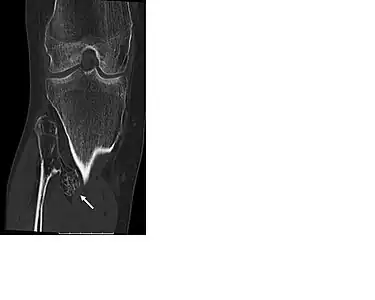

CT of osteochondroma in MO